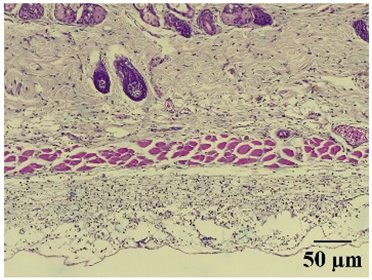

| 100× | 400× | Description | |

|---|---|---|---|

| Normal | ![]() | ![]() | Minimal leukocyte infiltration in the dermis, hypodermis, and subcutaneous tissue. Minimal leukocyte infiltration and slight alteration in the air pouch membrane thickness. |

| Control | ![]() | ![]() | Moderate presence of erythrocytes in subcutaneous tissue. Moderate leukocyte infiltration in the dermis, hypodermis, and muscle layer. Presence of eosinophils at the subcutaneous and muscular levels. Abundant leukocyte infiltration and intense alteration of the air pouch membrane thickness. |

| Indomethacin | ![]() | ![]() | Moderate leukocyte infiltration in the dermis and subcutaneous tissue. Moderate leukocyte infiltration and moderate alteration in the thickness of the air pouch membrane. |

| Mature hydrophilic 500 | ![]() | ![]() | Low leukocyte infiltration in the dermis and subcutaneous tissue. Low leukocyte infiltration and slight alteration in the thickness of the air pouch membrane. |

| Mature hydrophilic 1000 | ![]() | ![]() | Moderate infiltration of leukocytes in the dermis and subcutaneous tissue. Moderate leukocyte infiltration and moderate alteration in the thickness of the air pouch membrane. |